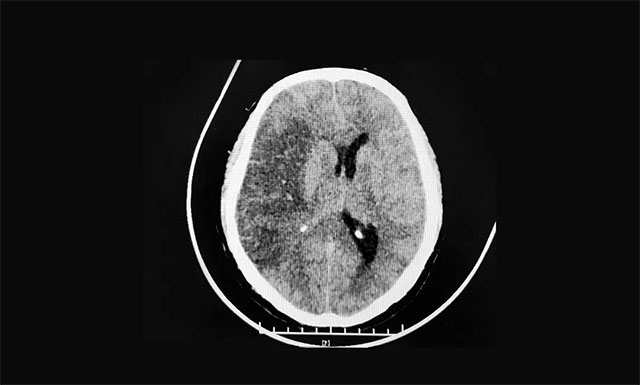

▲ 大面積出血性腦梗死

CT顯示,右側(cè)額顳頂枕葉(大腦中動脈供血區(qū))大面積出血性腦梗死,腦腫脹,右側(cè)高顱壓。蛛網(wǎng)膜下腔出血。針對患者病情,腦血管病病區(qū)主任張琪博士迅速在急診下為患者行右側(cè)顱骨去骨瓣減壓術(shù),術(shù)后患者病情逐漸平穩(wěn)。

張琪博士表示,出血性腦梗死是指腦梗死后梗死動脈再通恢復血液灌流,梗死灶繼發(fā)出血,頭顱CT表現(xiàn)為在原有的低密度病灶內(nèi)出現(xiàn)高密度影像。高血壓、大面積腦梗死、心臟病、房顫等高危因素與出血性腦梗死明顯相關(guān)。張琪博士提醒,出血性腦梗死起病較隱匿,臨床中易忽視,應多注意觀察病情,定期復查頭顱CT,以免漏診,貽誤病情。若出血量增加需按腦出血處理,如果占位效應明顯、腦水腫嚴重,可能出現(xiàn)腦疝,要及時行開顱手術(shù)治療。